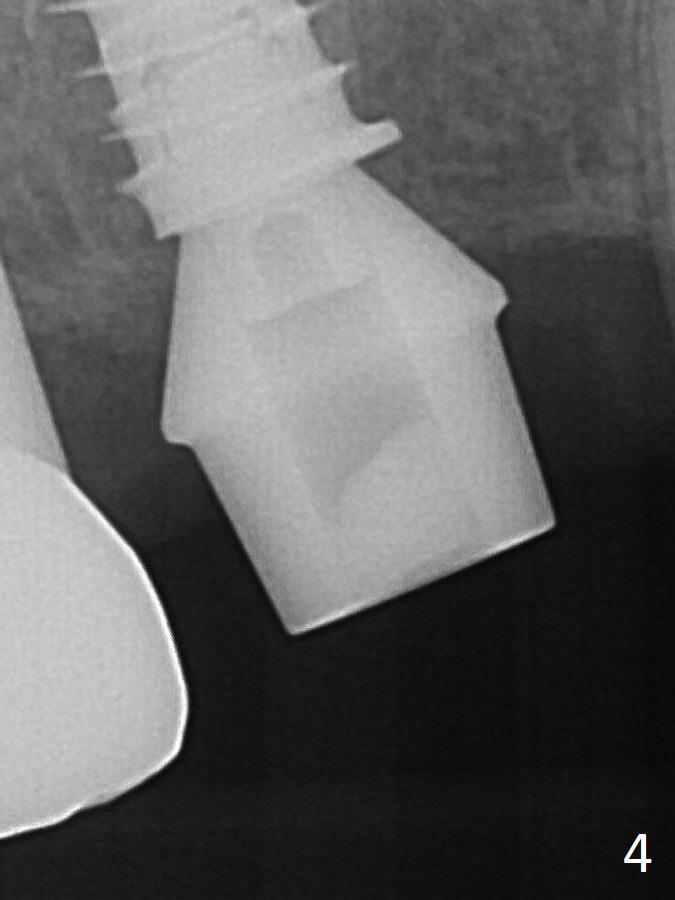

Fig.4: A 5.5x9 mm IBS implant is place with ~ 35 Ncm. A 6.5x4(3) mm abutment is placed immediately for an immediate provisional.